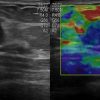

Ung thư tuyến vú

Ung thư tuyến vú - Ảnh 2

» Thông tin: Nữ giới – 45 tuổi.

» Lâm sàng: Kiểm tra sức khỏe.